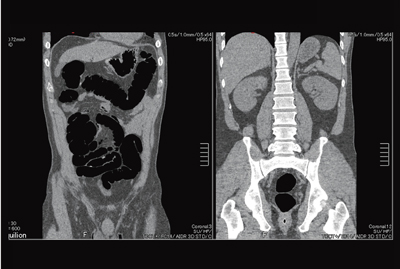

図2は,HP95(BP1.48)で撮影した大腸CTの画像である。腸管のガスや椎体からのアーチファクトが,高いレベルで抑えられているのがわかる。

図2 CTC Hi-Helical Pitch Scan(BP1.48,HP95)